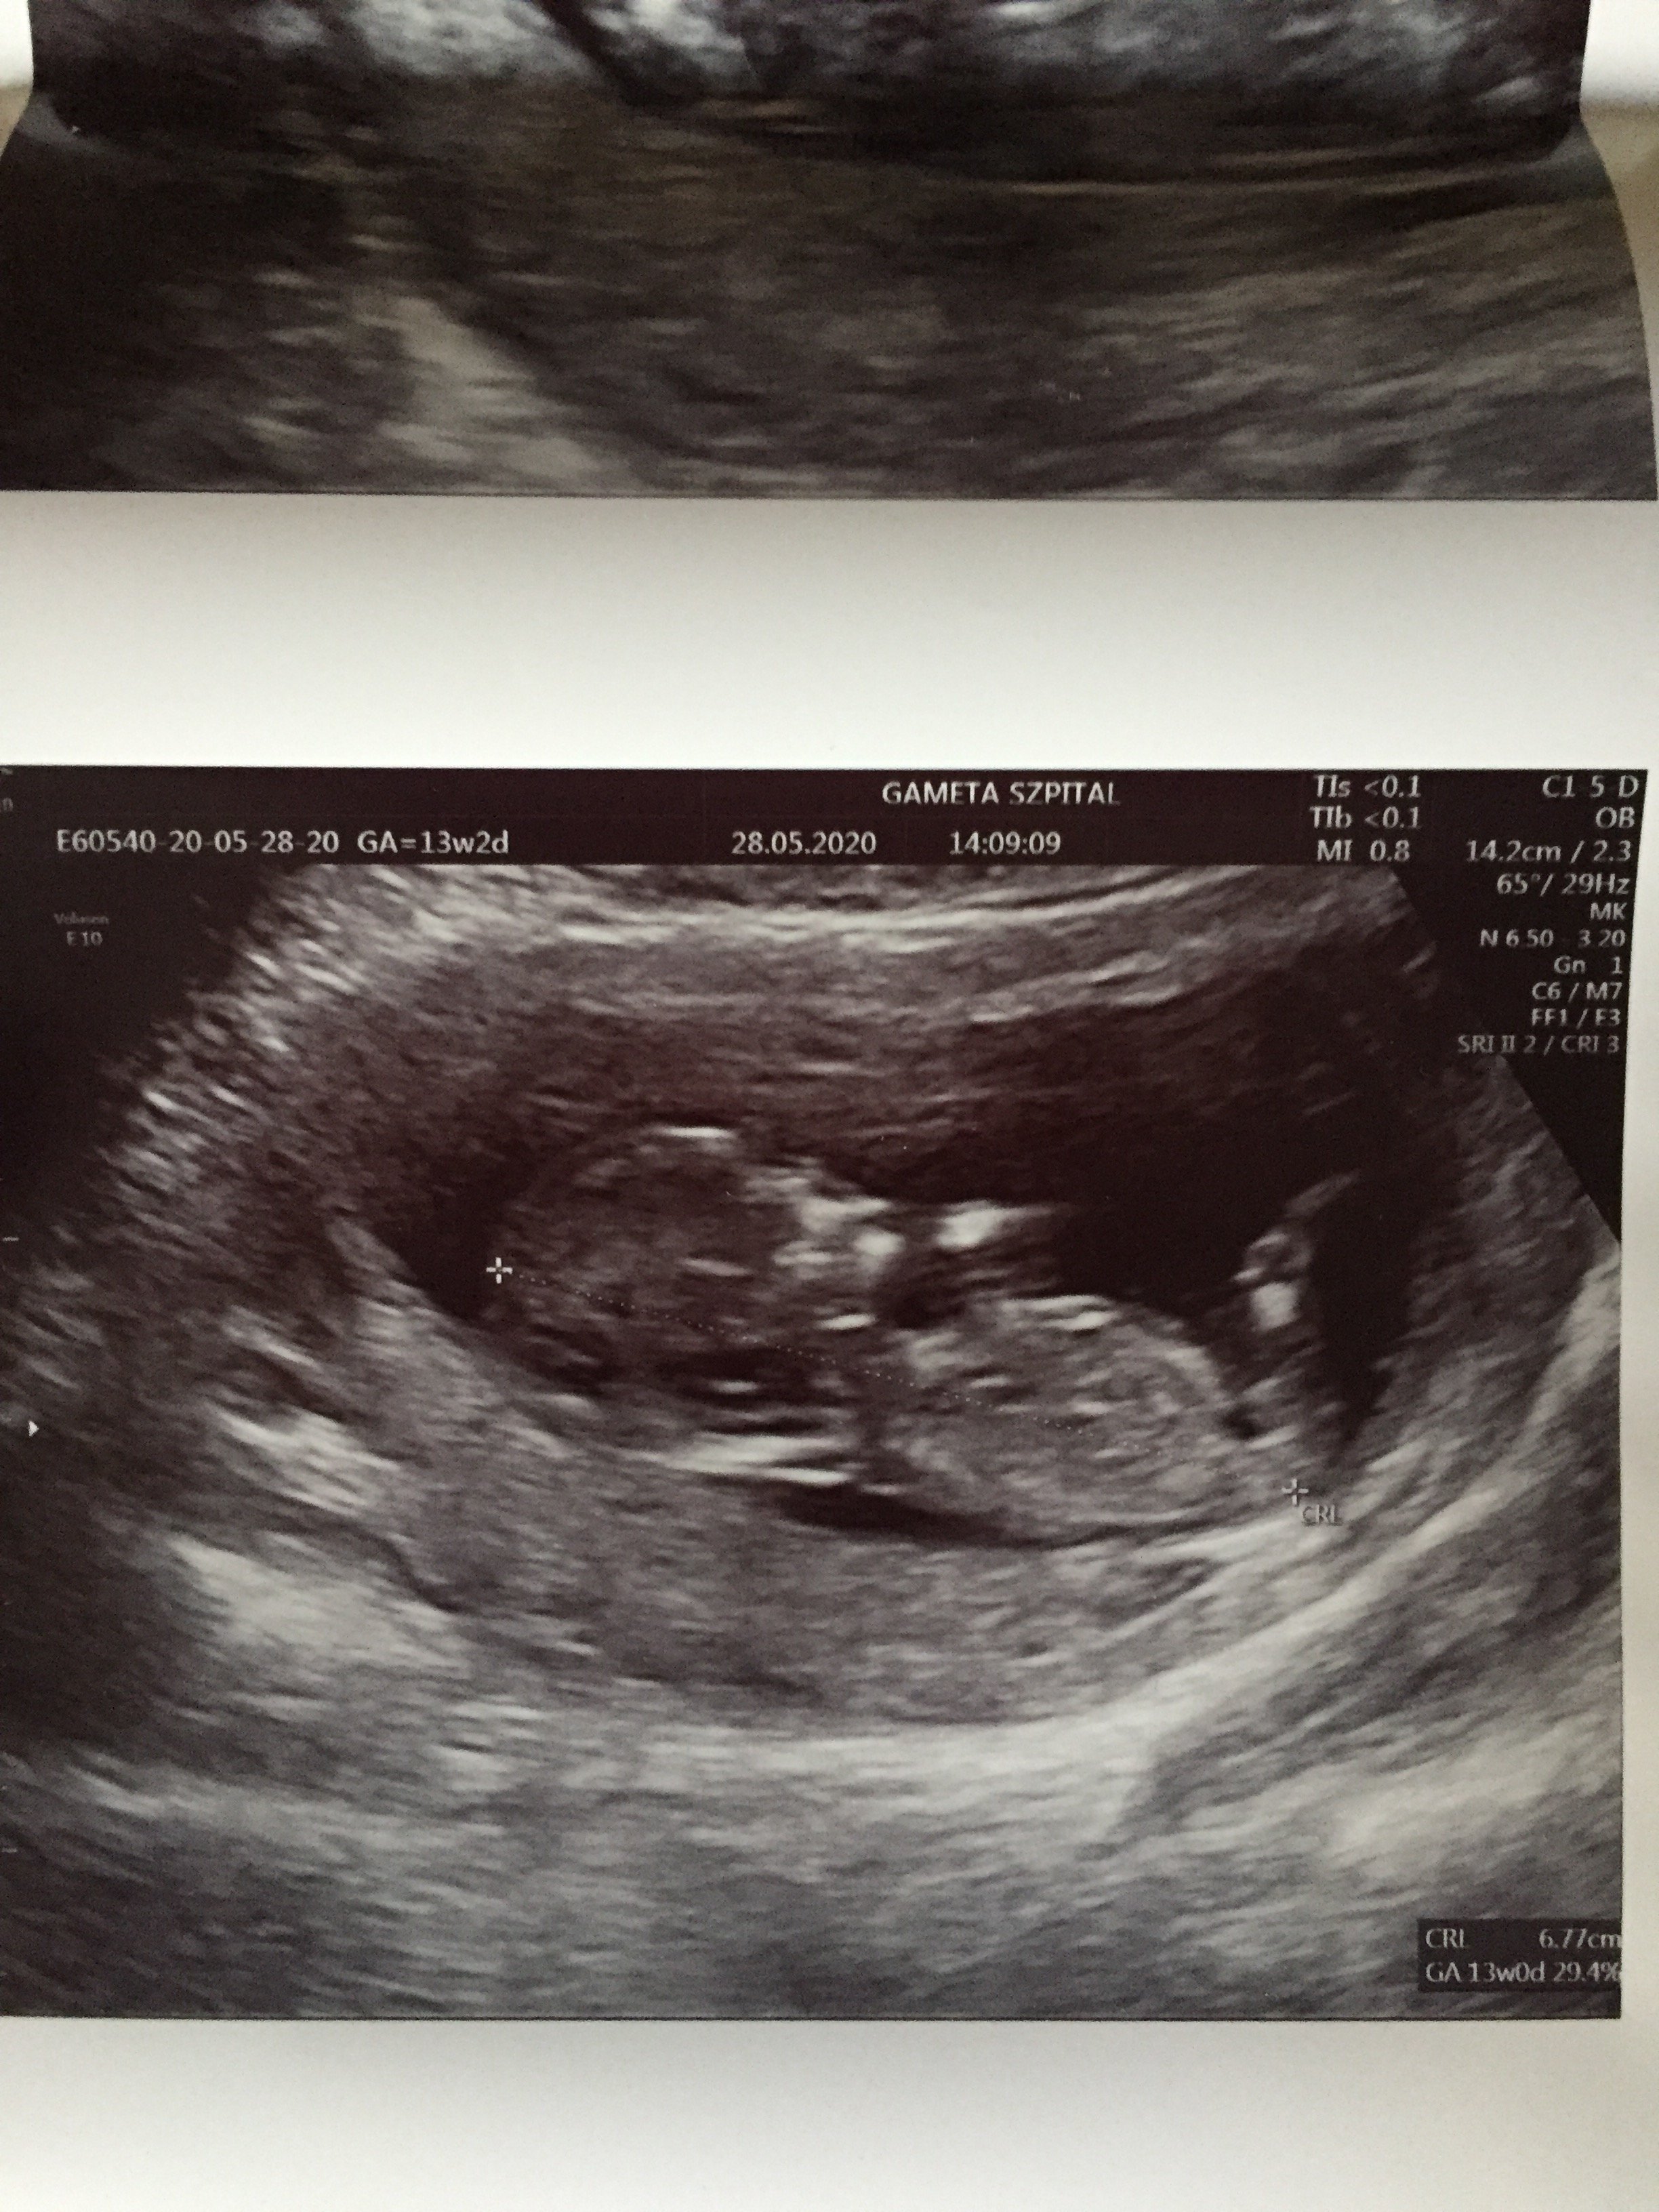

Kochana jesteś dobra w obstawianiu co u mnie widzisz ? 🤪 lekarz mówi dziewczynka a na ramxi nub różnie z przewaga na chłopaka 😂

Załączniki

• EDA5FDB8-E196-4175-94D7-862EF2D47AB9.jpeg

EDA5FDB8-E196-4175-94D7-862EF2D47AB9.jpeg

1,1 MB · Wyświetleń: 99